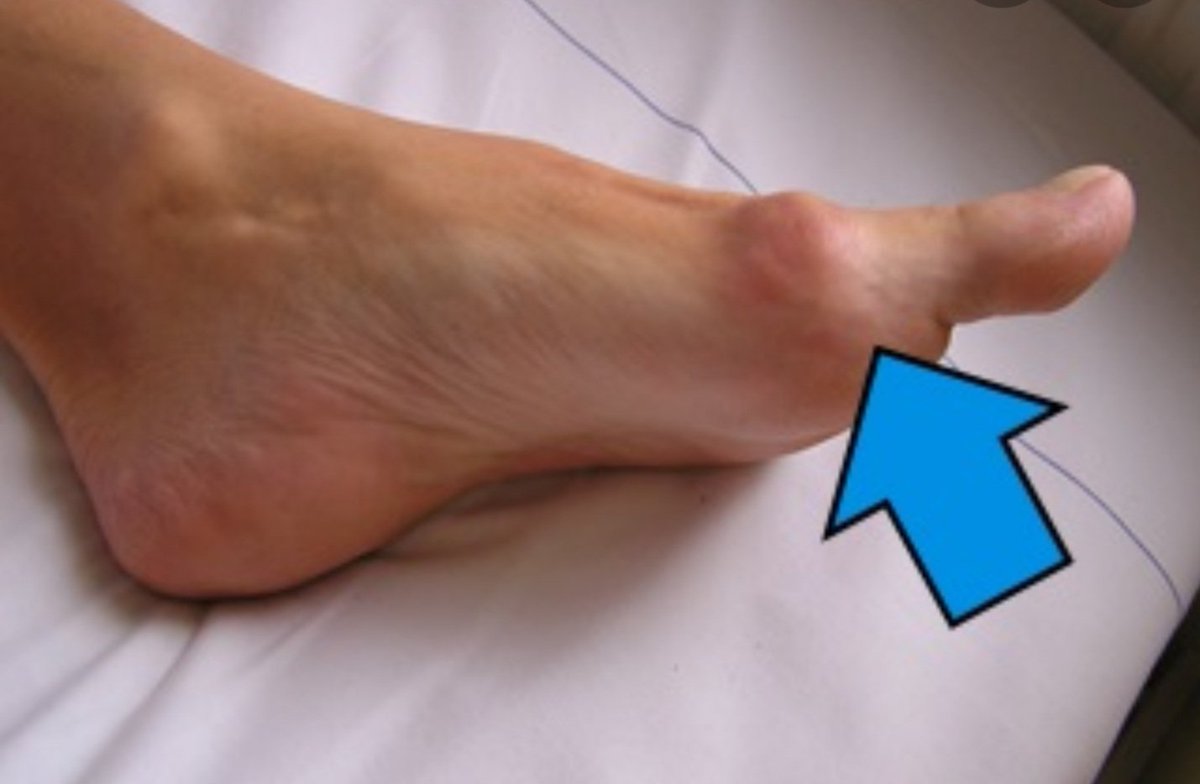

الفحص السريري:

-احمرار حول مفصل الأصبع الكبير

-انحراف واضح في الأصبع الكبير

-ضغط على الأصبع الثاني

-زيادة كبيره في عرض القدم